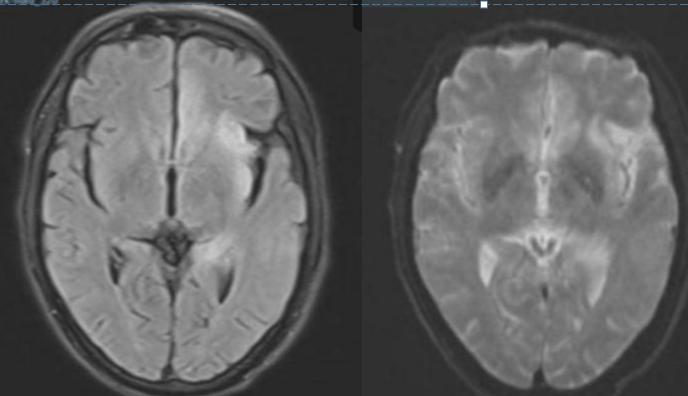

男性50岁,下午睡觉后家属喊不醒,大概4-5小时,之后反应淡漠,右下肢软瘫。

答案:神经梅毒。患者中年男性,急性起病,主要表现为反应迟钝,右下肢软瘫,头颅影像提示以双侧顶枕叶对称性高信号,左侧丘脑点状病灶,额颞叶萎缩。老师们想到了低血糖脑病、PRES、脑梗死、CO中毒等。小僧悟道老师一眼就看出来是梅毒,着实厉害。与年龄不相符的脑萎缩是重要特征。